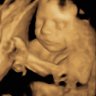

5+4 i går - målte pga blødning, men med såpass greit nivå + at hun kunne SE foster på UL i dag, så må jeg bare tro alt går bra!![]()

krysser fingrene for at det holder seg slikSå bra5+4 i går - målte pga blødning, men med såpass greit nivå + at hun kunne SE foster på UL i dag, så må jeg bare tro alt går bra!![]()